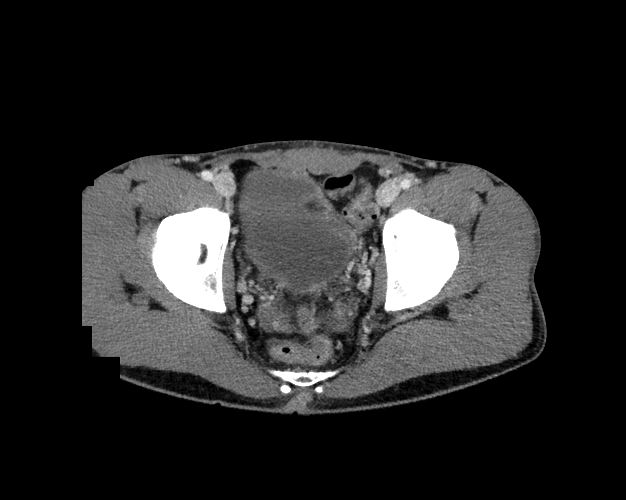

Body

Covers abdominal CT anatomy.